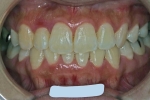

しかし、出題基準にも書いてあるように、このケースは欧米の白人によく見られるケースで、東洋人にはきわめて稀である。そこで類似ケースとして過蓋咬合(かがいこうごう)のケースを代替えとして認めるという配慮をしている。過蓋咬合とは非常に強く深く咬んでいる状態を言う。Overbiteとは前歯の垂直的な重なり具合を示す数値で、5mm以上だと上の前歯が下の前歯をほとんど覆い尽くしている感じになるので、前から見ると下の前歯はほとんど見えない状態になる。こういう状態が典型的な過蓋咬合である。典型的なclassⅡ,division 2のケースは過蓋咬合を合併している。

| マルチブラケット終了時